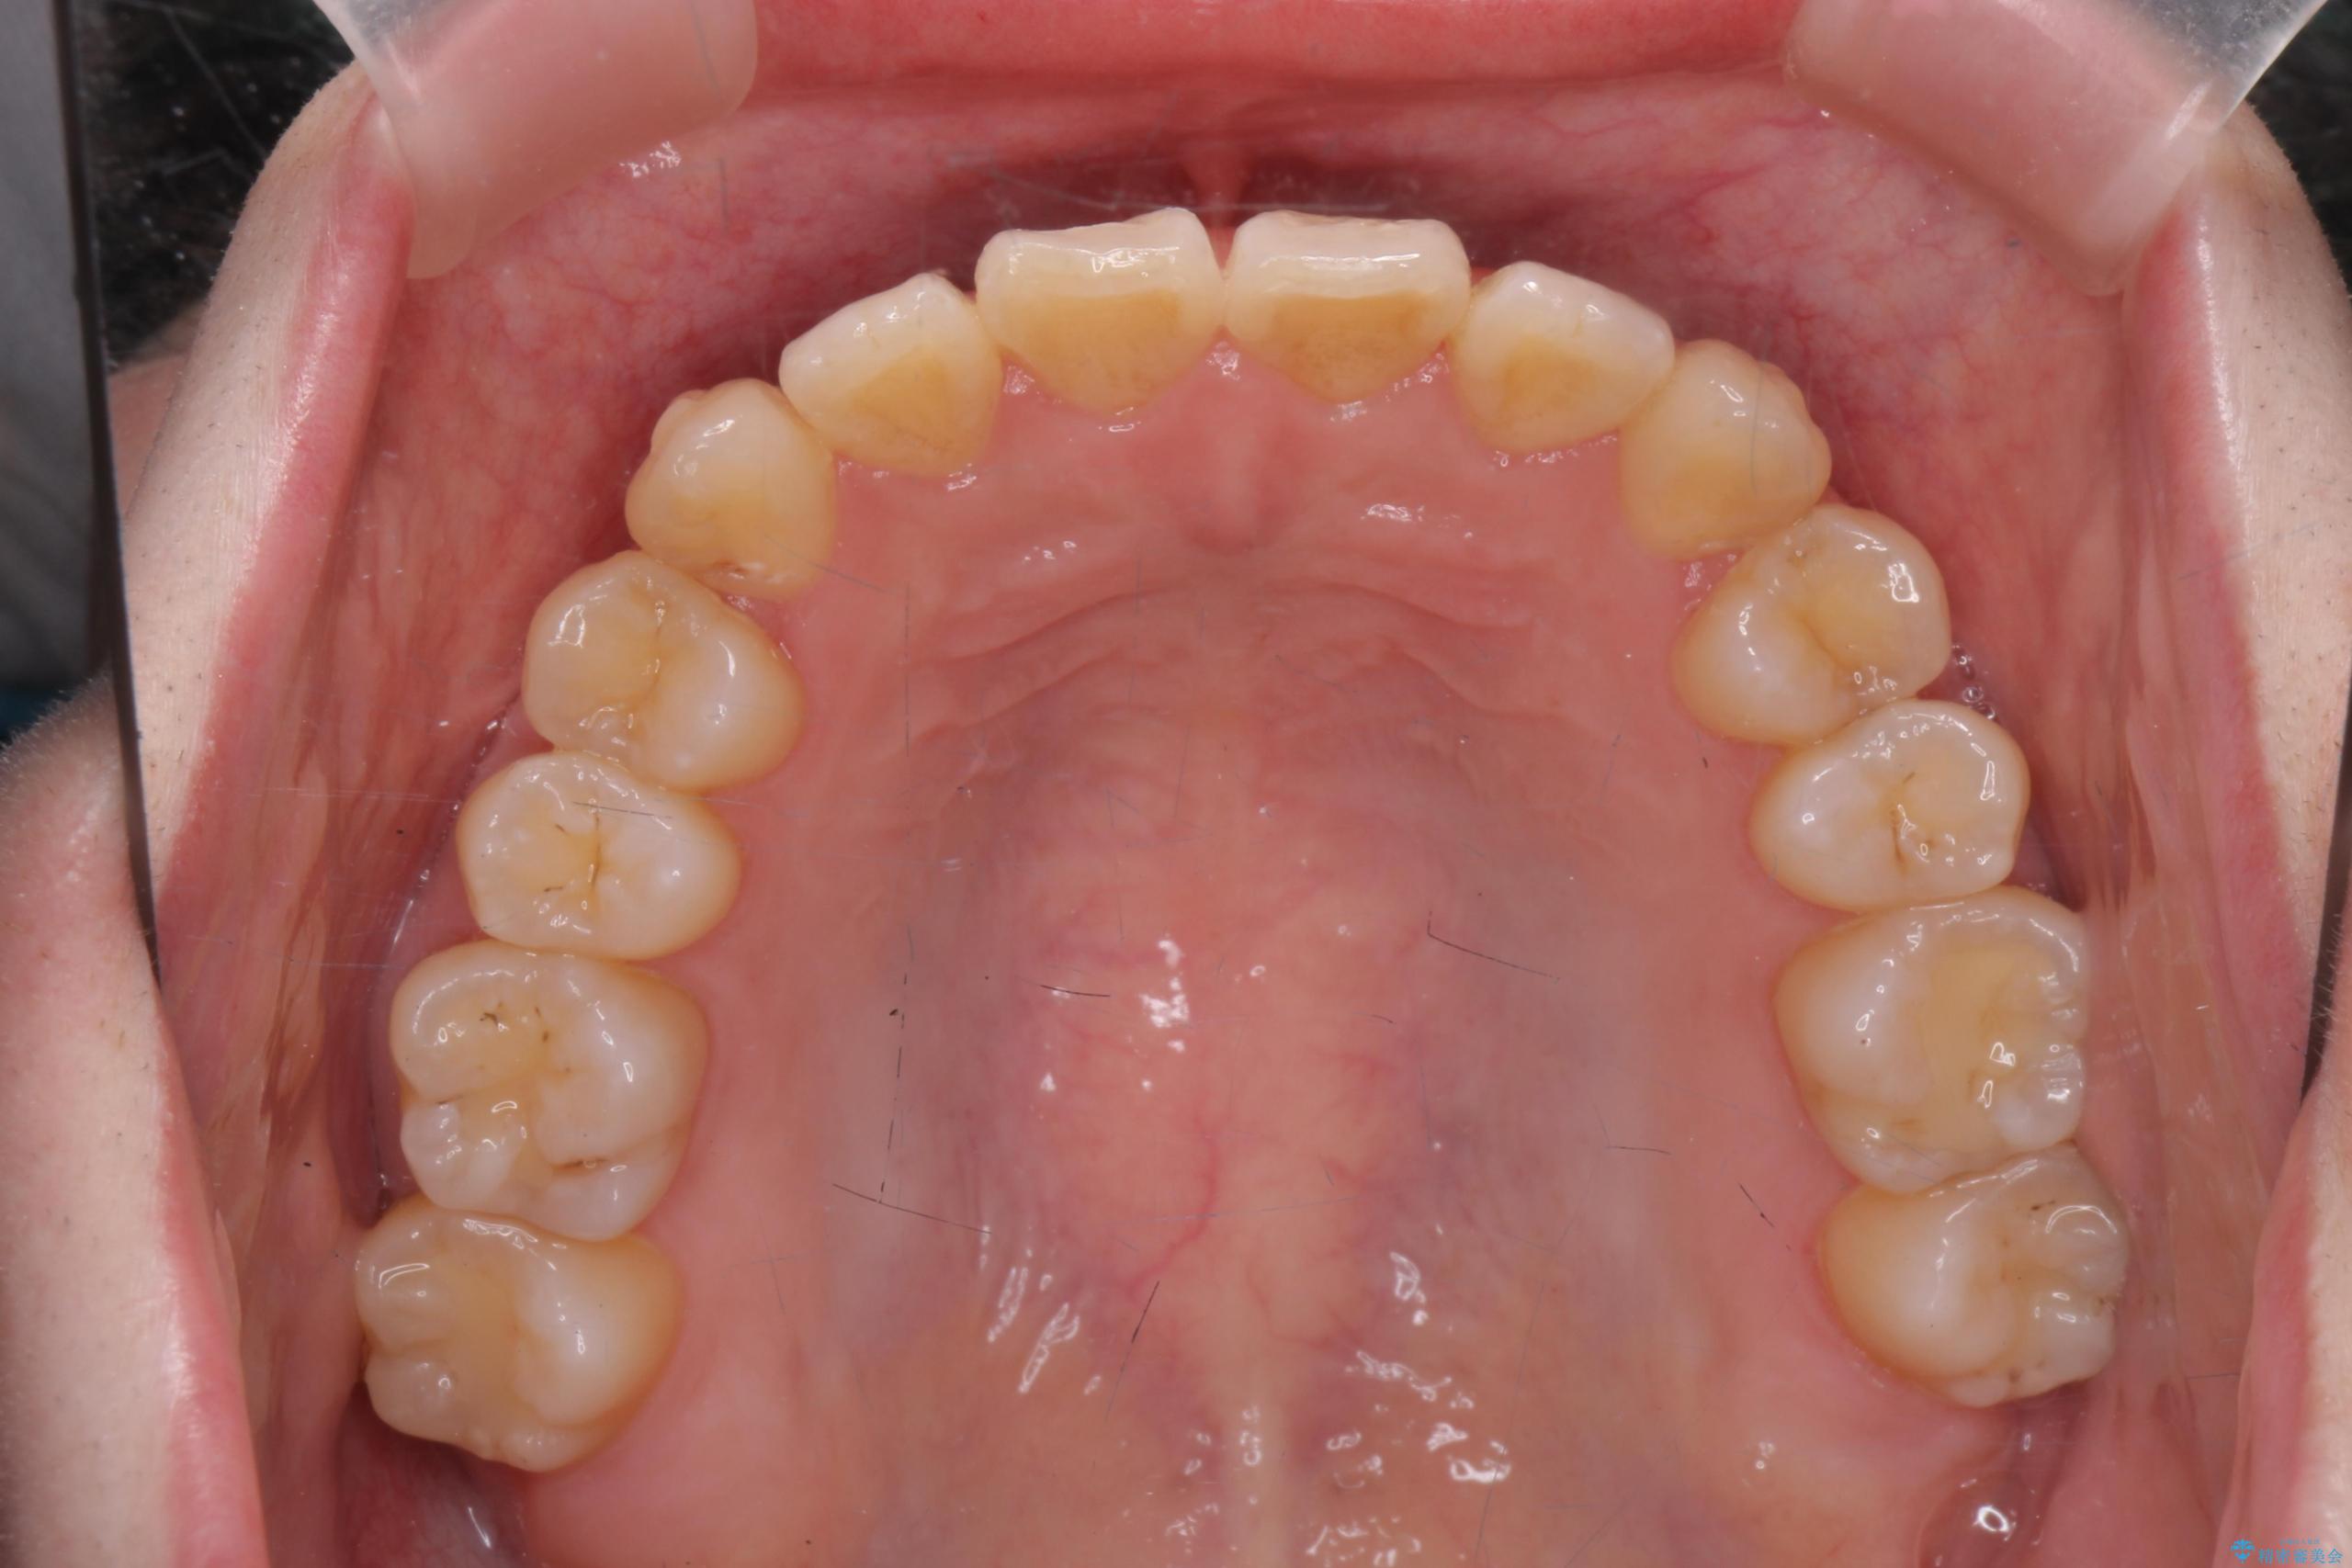

前歯のねじれが気になる、歯並びを改善したいとご来院された患者様です。

歯のねじれをきれいに取るのは、インビザライン(マウスピース矯正)だけでは難しい動きです。そのため、事前に4か月間の部分ワイヤー矯正を行い、治療期間を短くし、より美しい仕上がりを目指す計画です。

前歯が綺麗に並び、大変ご満足いただけました。